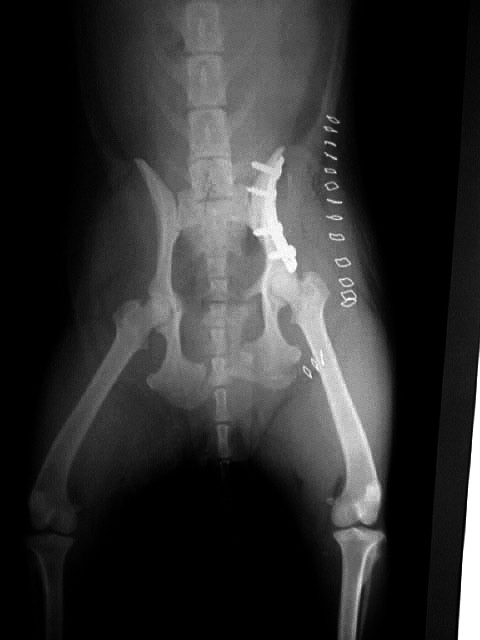

Beckenfaktur

Plattenrekonstruktion

Lendenwirbelfraktur L6

Fixation der Wirbelsäule mittels Querverbolzung durch beide Darmbeinflügel und Kreuzbein,

Drahtcerclage zwischen L6 und L7